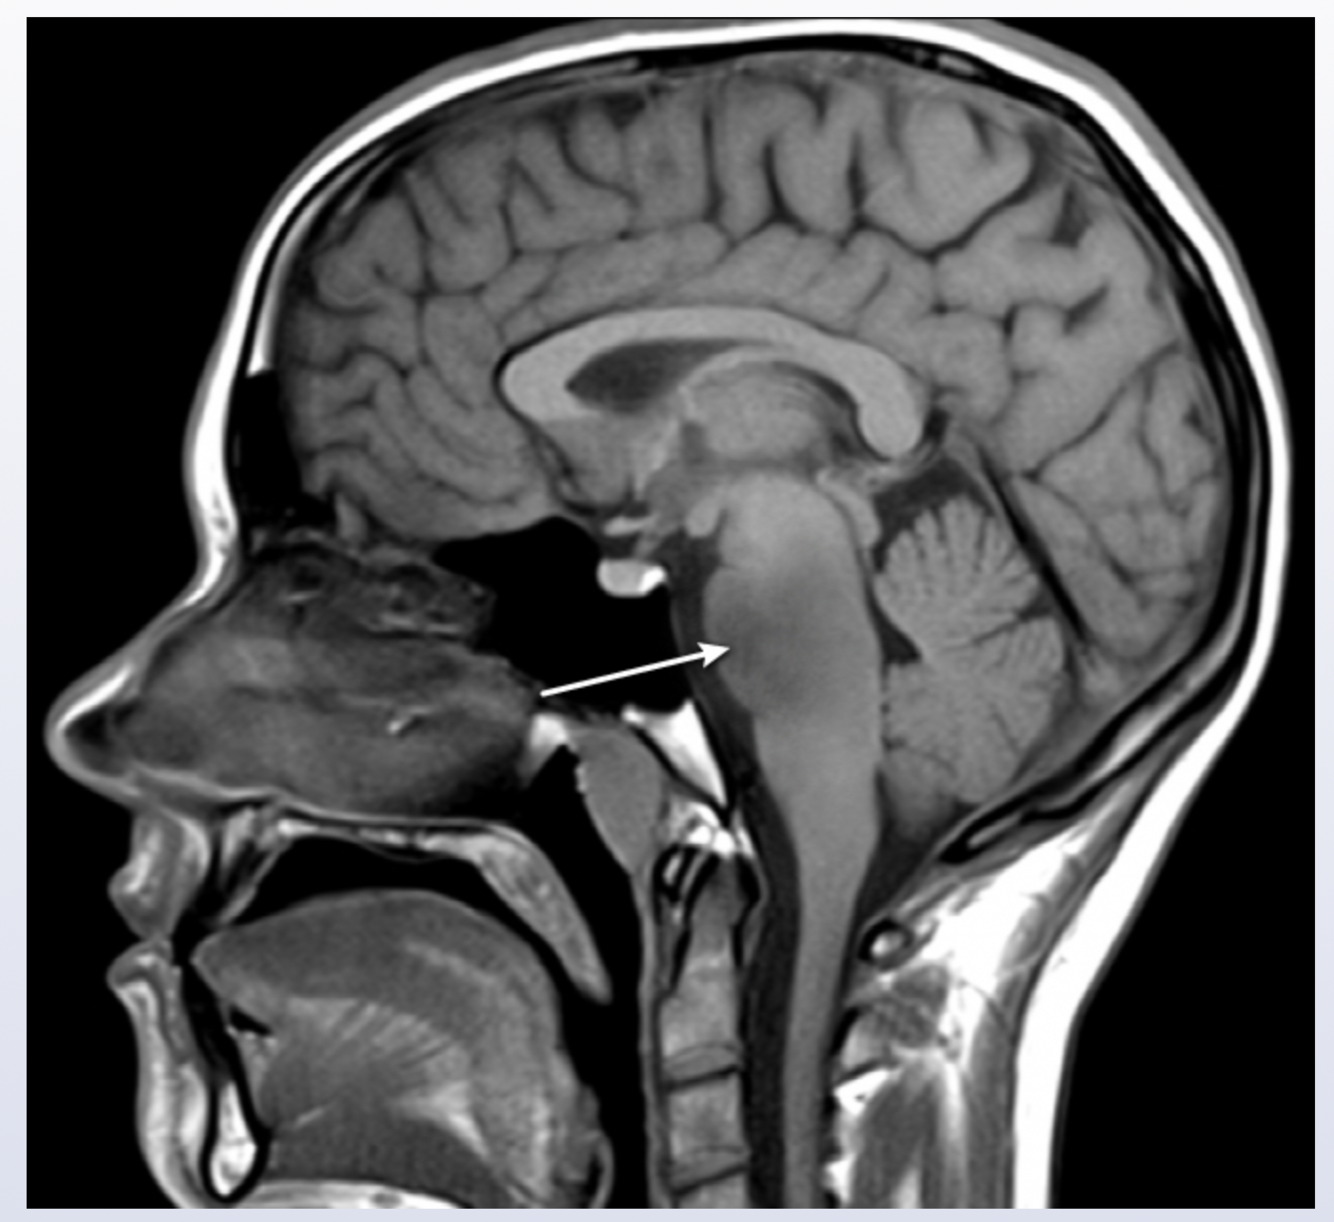

Pontine glioma

the nuclei of the vestibulococchlear nerve (CN VIII) are located in the pons; CN VIII conveys information about head position and movement and helps to stabilize the gaze during head movement; damage can lead to nystagmus